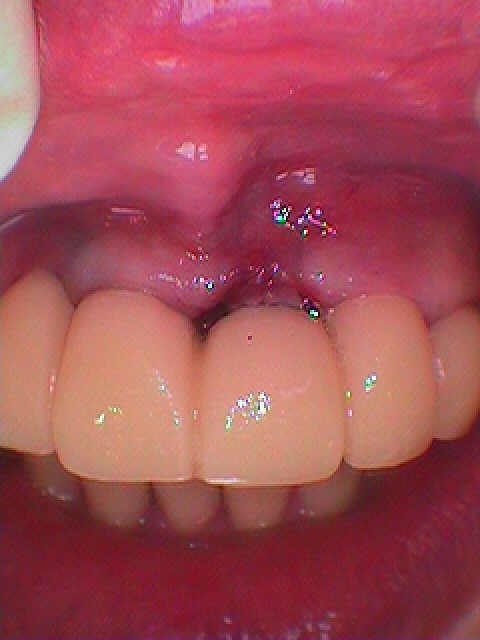

お知らせ|広島市安佐南区の歯科医院 > お知らせ トップ お知らせ・ブログ お知らせ スタッフブログ お知らせ お知らせ 2024/11/14 左上の7番部 近心根を抜歯して被せた歯が痛む 診てほしい 難関の最期臼歯部の抜歯即時インプラント治療 お知らせ 2024/11/13 左上の6、7番部のインプラントの上部構造まで お知らせ 2024/11/13 左上の6番部 嚙むと痛む診てほしい インプラント治療 1年以上待時 お知らせ 2024/11/12 左下の6番部のインプラント埋入から3か月 上部構造を仕上げていきます お知らせ 2024/11/12 左下の6番部のインプラント埋入 60代男性 お知らせ 2024/11/11 ジルコニアクラウンが入ってさらに5年が経ち、右上の2番部が動揺をし始めました 右上の2番部を抜歯をしてインプラントにて補強を行い、再度右上の1番部が持つように補綴をし直します お知らせ 2024/11/11 左上の1番部のインプラント埋入 右上1,2番部と左上1,2番部をジルコニアクラウンにて連結補綴していきます 嚙前歯の突き上げの動揺を抑えるためです 60代男性 お知らせ 2024/11/09 前歯部のブリッジの歯の動揺から欠損部へインプラント埋入を行っていきます お知らせ 2024/11/09 フルマウスのリコンストラクション 咬合再構成を行った最終補綴まで お知らせ 2024/11/08 残存歯が少なくインプラント治療との併用にて咬合再構成を行ったケースになります << 1 2 3 4 5 … 16 17 18 19 20 … 485 486 487 488 489 >> Web診療予約 初めての方へ 選ばれ続ける理由 院内設備について 歯が痛いしみる一般歯科 歯がぐらぐらする歯周病 健康な歯を保ちたい予防歯科 子供の虫歯予防をしたい小児歯科 銀歯をセラミックに審美歯科 白い歯を目指しませんか?ホワイトニング 矯正専門医がいるので安心矯正歯科 抜けた歯を補いたいインプラント・入れ歯 医院案内 スタッフ紹介 メリィハウス歯科クリニックオフィシャルホームページ ラベンダー歯科クリニックオフィシャルホームページ お知らせ・ブログ ホーム 診療科目 一般歯科 歯周病治療 予防治療 小児歯科 審美治療 ホワイトニング 矯正歯科 入れ歯・インプラント マウスピース矯正 初めての方へ 院長・スタッフ 設備紹介 医院案内・アクセス メニューを閉じる